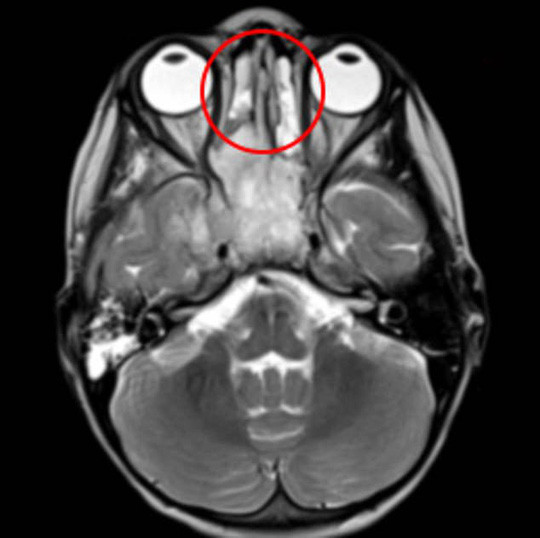

| Khối u (khoanh tròn đỏ) được thể hiện trong phim MRI - ảnh do bệnh viện cung cấp |

Cuối cùng, bé được đưa đến Bệnh viện Frimley Park để chụp MRI. Các bác sĩ đã phát hiện một khối u lớn trong khoang mũi. Bé bị chẩn đoán mắc bệnh ung thư khoang mũi hiếm gặp. Căn bệnh tấn công xương và một phần mô bên trong khoang mũi, thậm chí đã lan một ít đến vùng xương sọ, cơ hàm và cả một số tế bào não bộ.